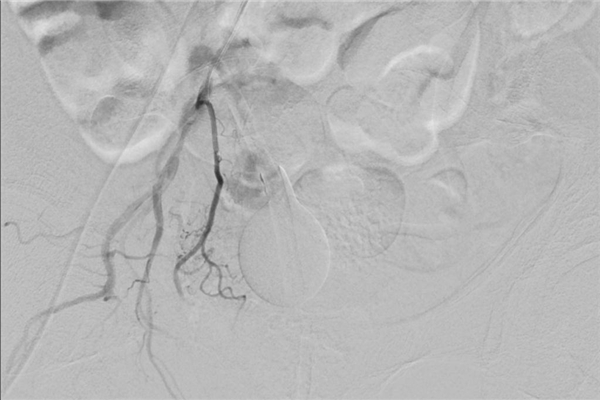

后经左侧前列腺动脉插入微导管造影,可见迂曲的动脉(如下图),这给手术增加了一定难度。

下图中,红色箭头所指为前列腺动脉,绿色箭头所指阴影部位为增生的左侧前列腺染色。